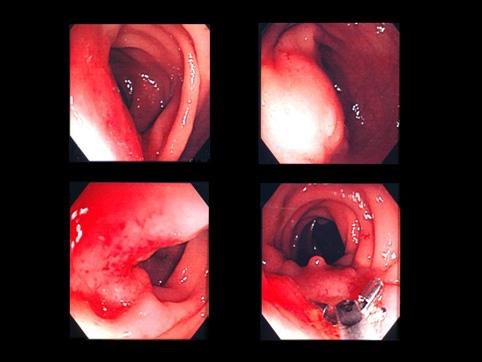

症例提示(所在地,施設名等): 佐賀県・ 佐賀県立病院好生館 (梶原先生からの提供症例)

疾患(病理主体)の分類腫瘍様病変/子宮内膜症

部位(臓器別)大腸/直腸

検査方法内視鏡

病変の最大径(ミリ)40以上